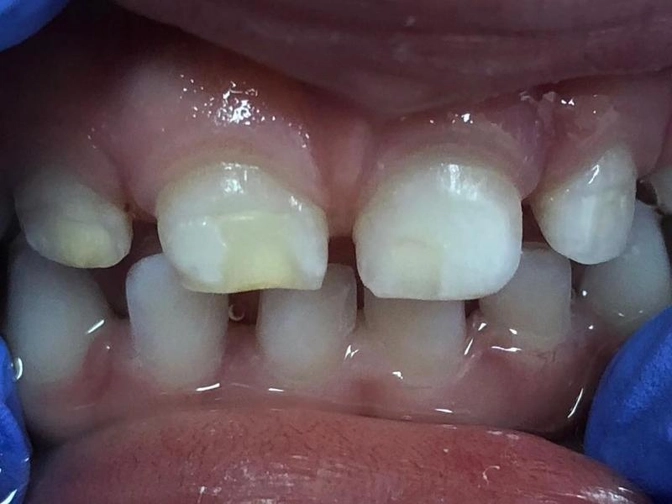

Гипоплазия эмали.

Это ГИПОПЛАЗИЯ.

Часто ее путают с кариесом.

Дело все в том, что в отличие от кариеса, который не может появиться до прорезывания зубов, т.е. быть врожденным, гипоплазия как раз возникает задолго до прорезывания зубов - в период их закладки и минерализации.

ВАЖНО! Прорезывание у ребенка зубов с гипоплазией эмали - высокий риск кариеса!

Важно знать, что на фоне гипоплазии эмали кариес развивается в разы интенсивнее, процесс очень агрессивный, может затрагивать одновременно несколько полостей зубов.